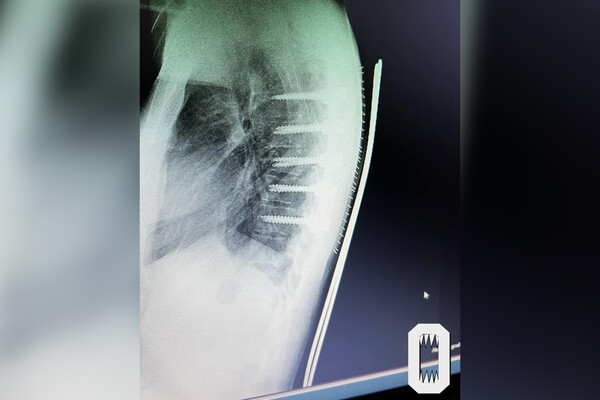

Как рассказала 21-летняя потерпевшая, в августе 2024 года она отправилась на отдых в Бодрум по путевке туроператора Anex. Девушка утверждает, что по приезде приобрела у представителя компании билет на экскурсию, на которой предполагалась прогулка по реке Дальян и осмотр ущелья. 8 августа, в день тура, водитель автобуса, в котором находилась девушка, не справился с управлением и улетел в кювет. 21-летней россиянке потребовалась помощь скорой: ее доставили в больницу города Милас, где диагностировали ей перелом позвонка грудного отдела. Во время операции ей установили титановые штифты.